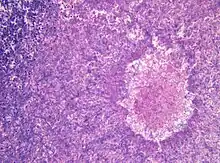

Although most fungi—and especially Aspergillus—fail to grow in healthy human tissue, significant growth may occur in people whose adaptive immune system is compromised, such as those with chronic granulomatous disease, who are undergoing chemotherapy, or who have recently undergone a bone marrow transplantation. Within the lungs of such individuals, the fungal hyphae spread out as a spherical growth. With the restoration of normal defense mechanisms, neutrophils and lymphocytes are attracted to the edge of the spherical fungal growth where they lyse, releasing tissue-digesting enzymes as a normal function. A sphere of the infected lung is thus cleaved from the adjacent lung. This sphere flops around in the resulting cavity and is recognized on x-ray as a fungus ball. This process is beneficial as a potentially serious invasive fungal infection is converted into surface colonization. Although the fungus is inactivated in the process, surgeons may choose to operate to reduce the possibility of bleeding. Microscopic examination of surgically removed recently formed fungus balls clearly shows a sphere of dead lung containing fungal hyphae. Microscopic examination of older lesions reveals mummified tissue which may reveal faint residual lung or hyphal structures.[4]